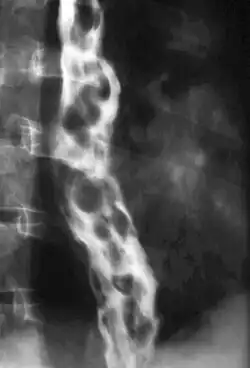

Varizes esofágicas

| Imagem endoscópica de varizes esofágicas com manchas vermelhas | |

Varizes esofágicas são dilatações das veias do esôfago. São relacionadas em geral com a cirrosee a esquistossomose e outras doenças que provocam hipertensão da veia porta e podem se romper e provocar hemorragias renais.